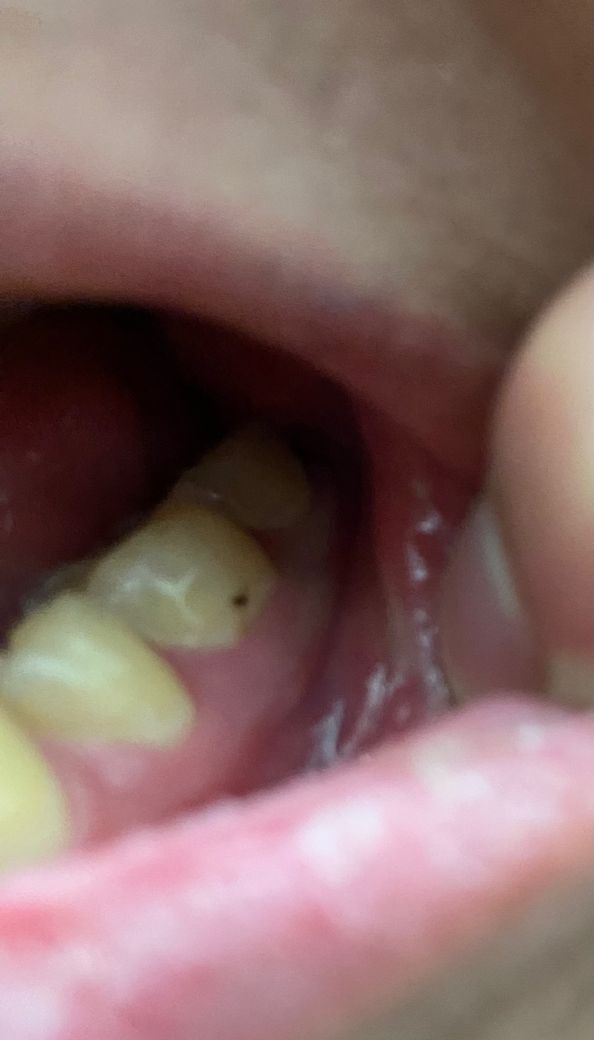

왼쪽 어금니 아래쪽에 검은 점 같은 게 생겼는데 충치일까요?

사진과 같이 왼쪽 어금니 아래에 저런 점이 생겼습니다.

저 치아 윗부분은 이전에 충치가 발생해 레진으로 때웠습니다.

저 치아 윗부분은 약간 금이 간 것처럼 느껴지기도 합니다.

저 정도의 크기면 약간 갈아내고 때우기만 하면 되는 수준의 충치일까요?

사진 상으로는 아래 치아 중 오른쪽 두번째에 저런 것이 생겼습니다.